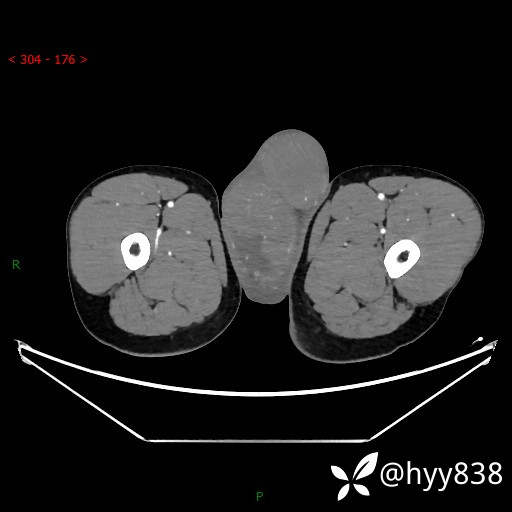

静脉期